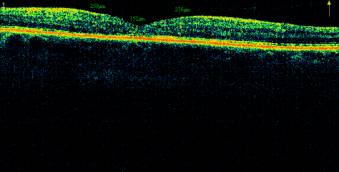

Рис.5.

Глазное дно и ОКТ макулы пациента М., 52г. с ППДР с разрешившимся ДМО

после комплексного лечения и ЛК.